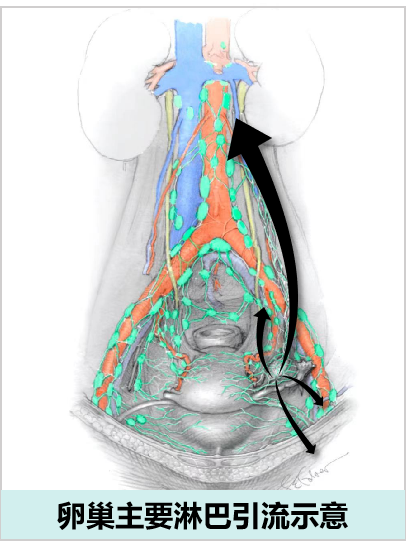

卵巢淋巴引流

自卵巢门发出输出淋巴管,卵巢淋巴引流的三大途径:

• 自卵巢门至腰淋巴结(上行途径):自卵巢门发出6~8条淋巴管,沿骨盆漏斗韧带与卵巢血管伴行上升,终止于第1、2腰椎水平的高位腹主动脉旁和肾静脉区域的腰淋巴结,为卵巢淋巴回流最主要途径。

• 自卵巢门至髂内、髂外及髂总淋巴结(下行路径):一部分淋巴管自卵巢门发出后于宫旁走行,在阔韧带内与子宫血管的卵巢支伴行通往盆腔,止于髂内、髂外及髂总淋巴结。当主要通路受阻时,淋巴液可沿此途径至盆腔淋巴结。

• 自卵巢门至腹股沟淋巴结:极少数淋巴管可沿圆韧带引流至腹股沟淋巴结。